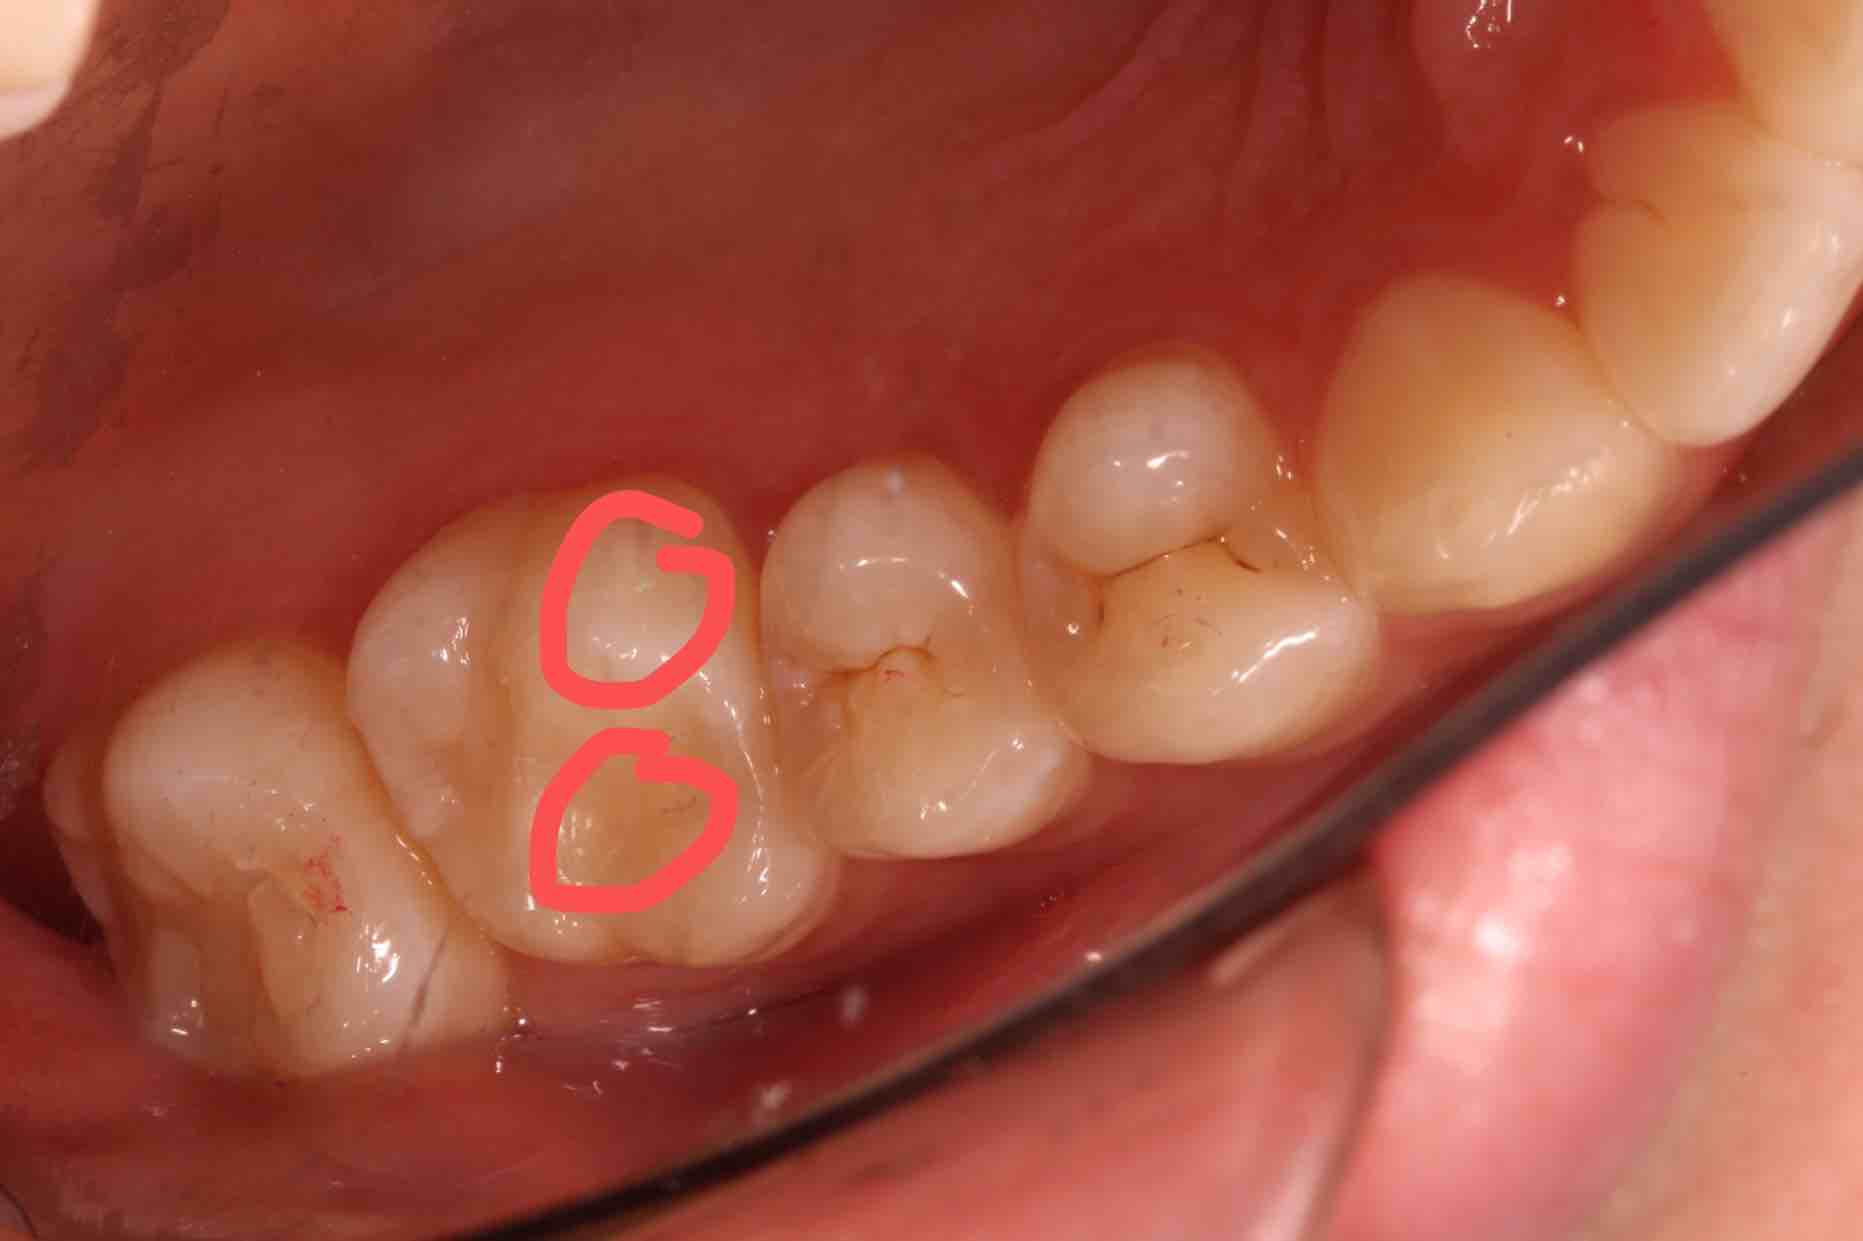

铒激光微创补牙 :这样的窝沟点隙,有点龋坏,用球钻去除,破坏好牙有点多,不忍心;有没有更好的办法呢,用铒激光去除龋坏,专心、专业去除坏牙,还有杀菌、消毒、脱敏的功效,减少补牙术后敏感症状及继发龋坏的发生,另外还有酸蚀的作用,减少了化学药物的影响;没有窝轮机的振动,非常轻柔的啪啪的响声,能够高效、微创去除龋坏,高科技一铒激光微创补牙,您值得拥有!